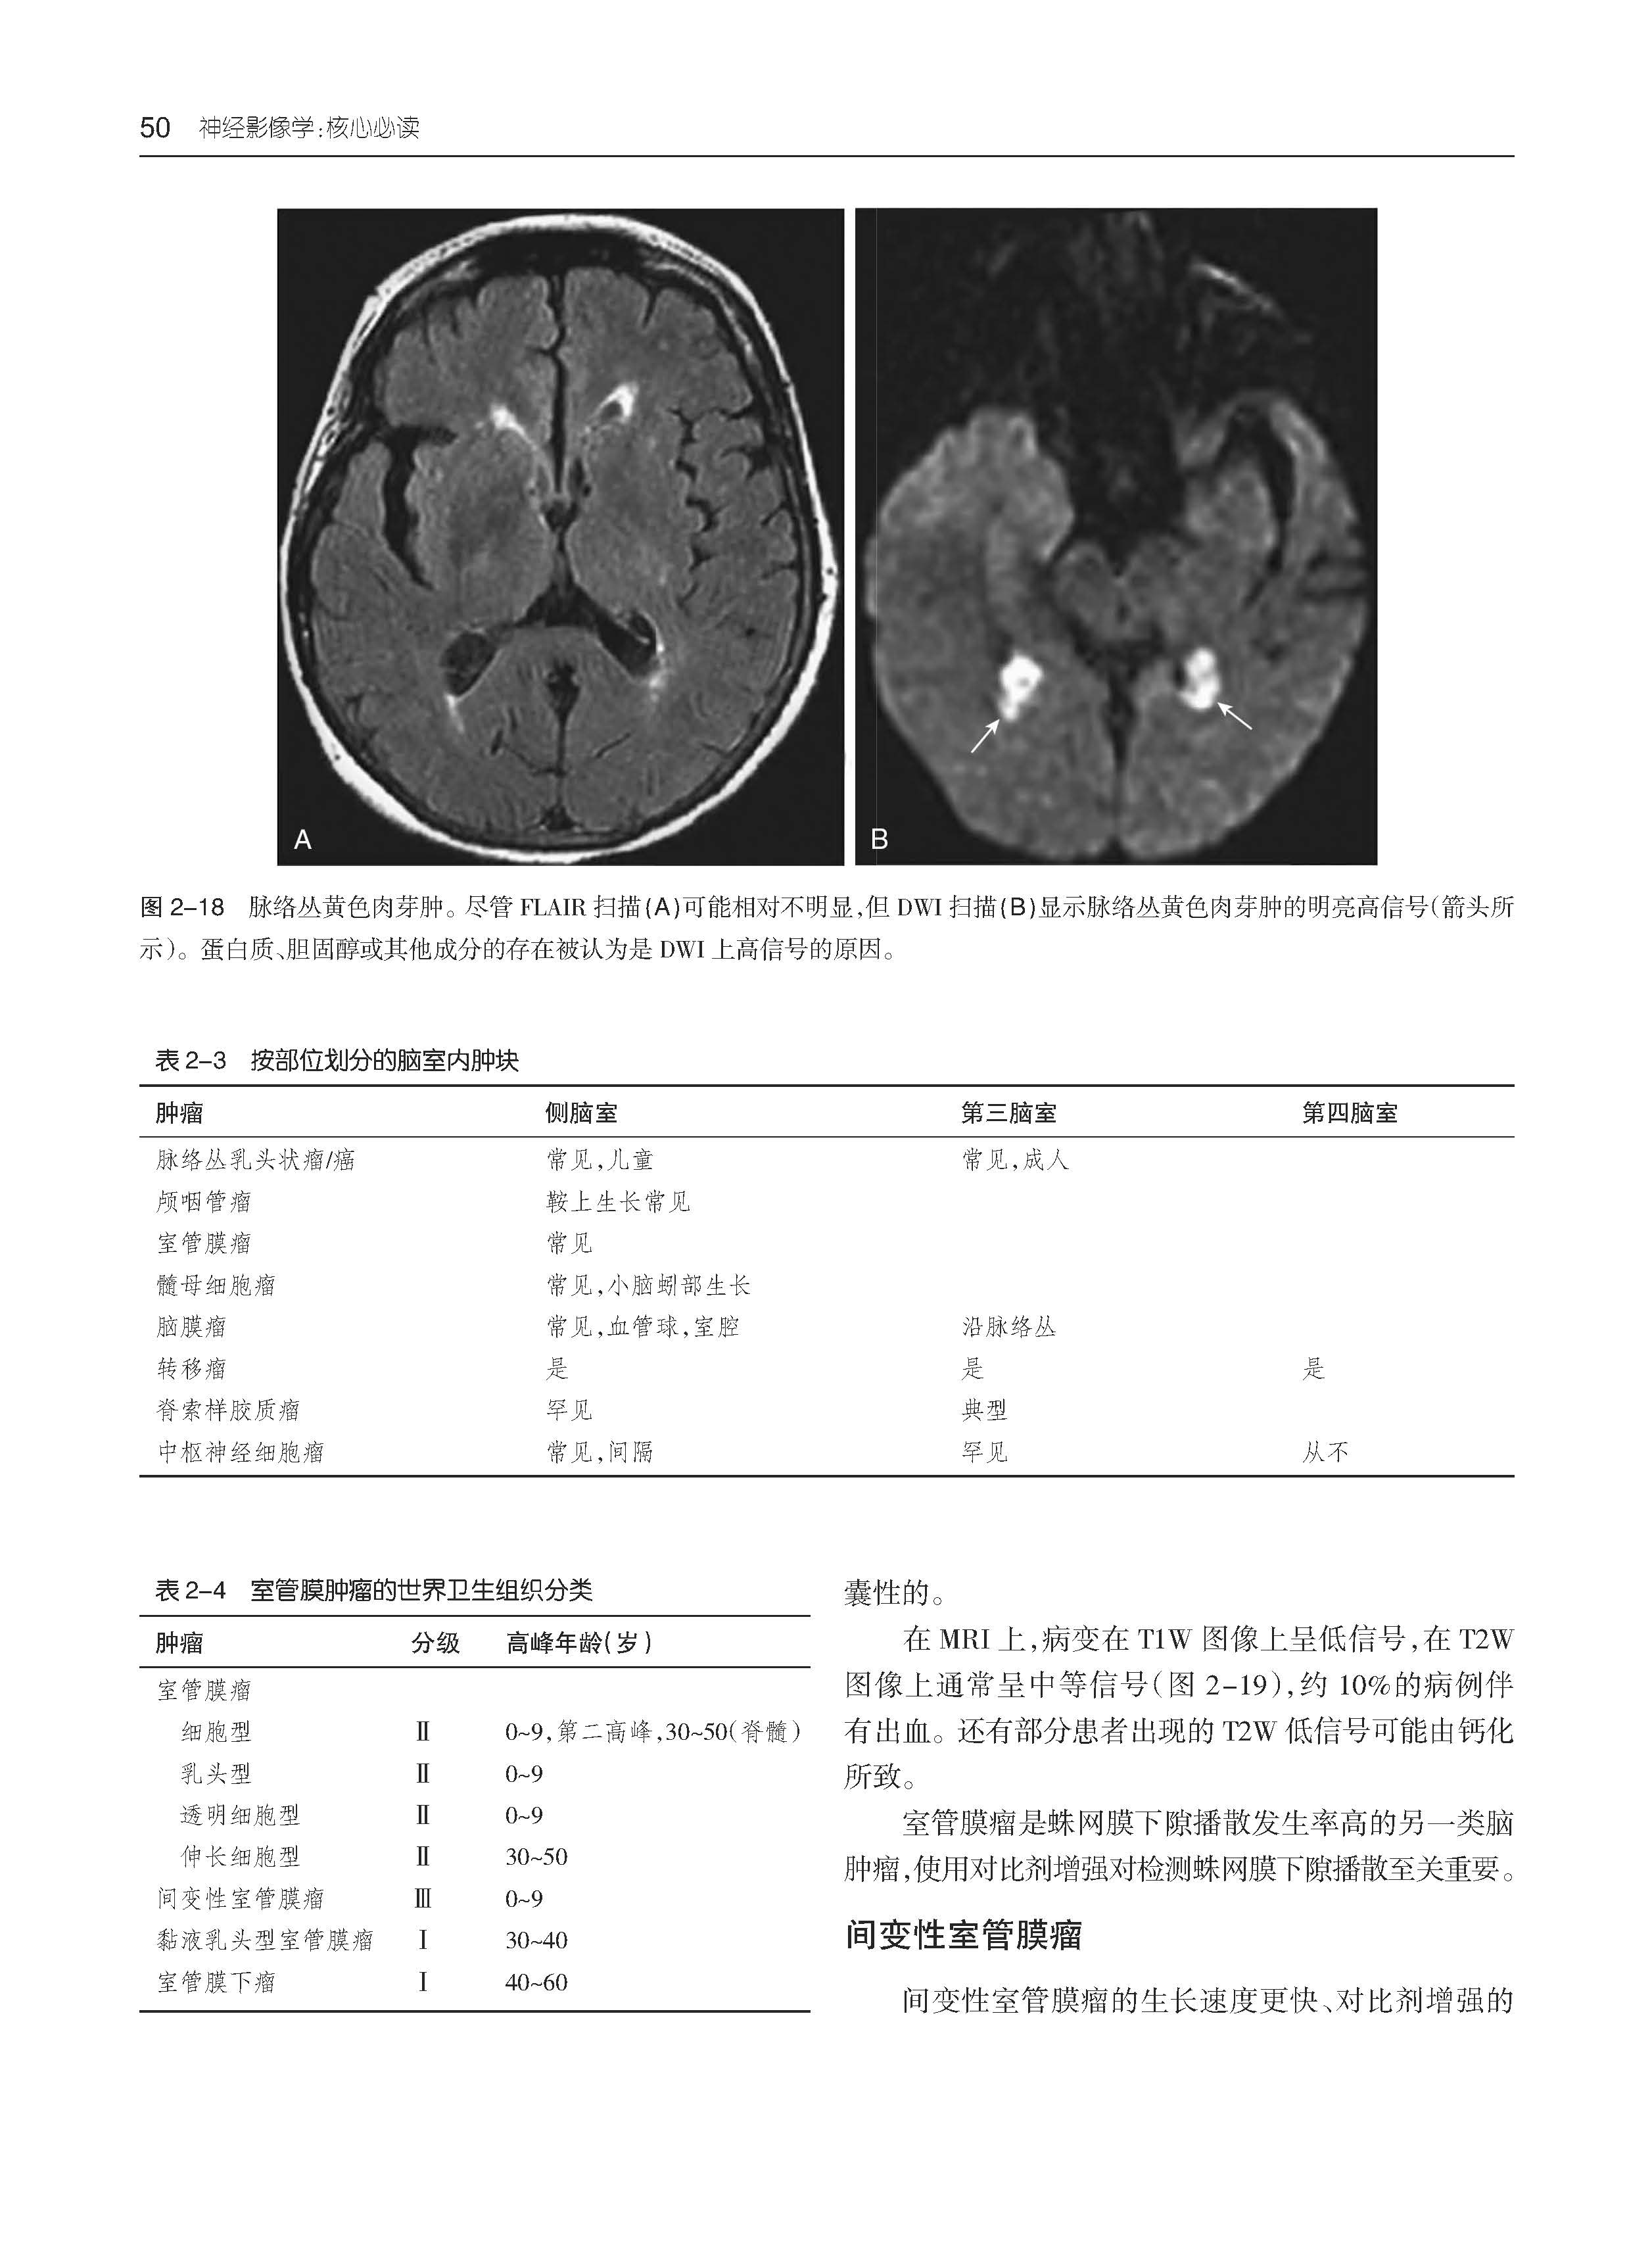

·图文并茂 全书共1200余幅高清图像,直观地呈现病变特征和诊断要点。